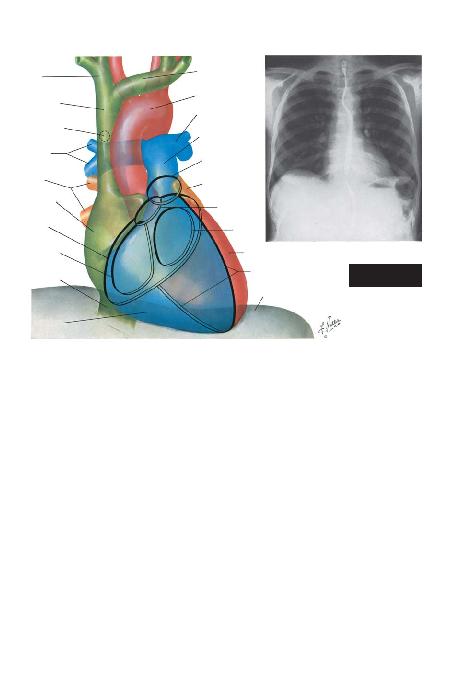

BÖLÜM I -- LEVHA 21

(Sayfa 23'ten devam ediyor)

SA/ BRAKVEN

SOL BRAKVEN

SOL PULMONER

ARTER

PULMONER

TRUNK

PULMONER KAPAK

HALKASI

SOL ATRUZANTI

AORTHALKASI

MHALKASI

SULKUS

AORTA

SOL VENTRÜKÜL

D

SUPERVENA KAVA

AZVEN OR

SA/ PULMONER

ARTERLER

VENLER

ATRSULKUS

TRHALKASI

VENA KAVA

SA/

VENTR

SA/ ATR

KALBANTEROPOSTERYORUMLANMASI